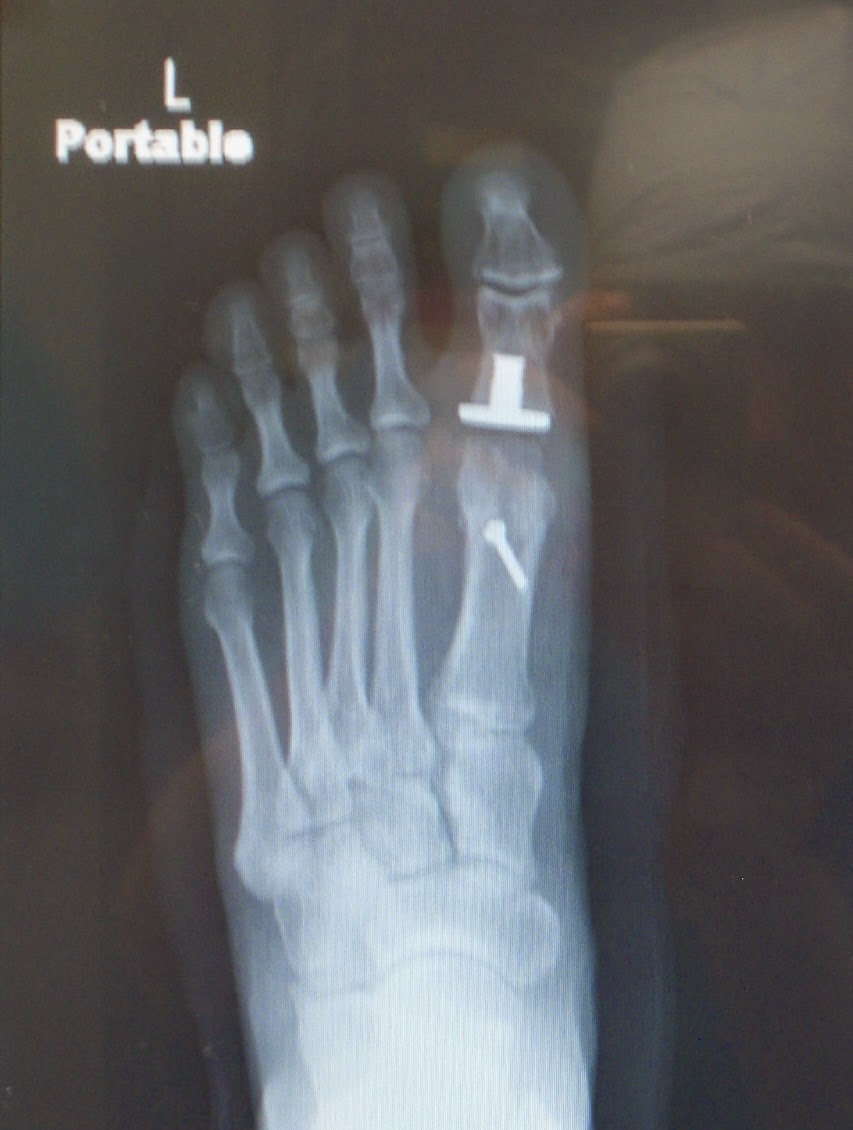

El caso de hoy es el de un hombre operado de Hallux Valgus en ambos pies por dos veces. El paciente es de fuera de Salamanca y después de haberlo operado en dos ocasiones cada pie, el pobre quedó peor de lo que estaba con su Hallux Valgus, formándosele un Hallux Límitus-Rígidus iatrogénico en ambos pies.

Al paciente le realizaron por lo que veo en las radiografías e intraoperatoriamente un Keller, un y una osteotomía capital pero que elevó la cabeza de los metatarsianos. La intervención que yo le he realizado va encaminada a darle movilidad de nuevo al primer dedo y a plantaflexionar el primer radio.

Para ello le he realizado una osteotomía de Austin Youngwick de brazo largo y le he colocado un hemi implante.

Comprobación radiológica de la zona intervenida con el implante colocado y la osteosíntesis. Comprobación intraoperatoria.

Radiografía final post operatoria.Radiografía pre operatoria y.........

.....radiografía post operatoria.